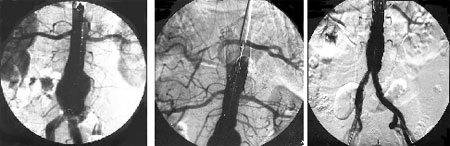

İkinci hastamızın işlem öncesi, işlem sırasında ve işlem sonrası anjiografik görünümü